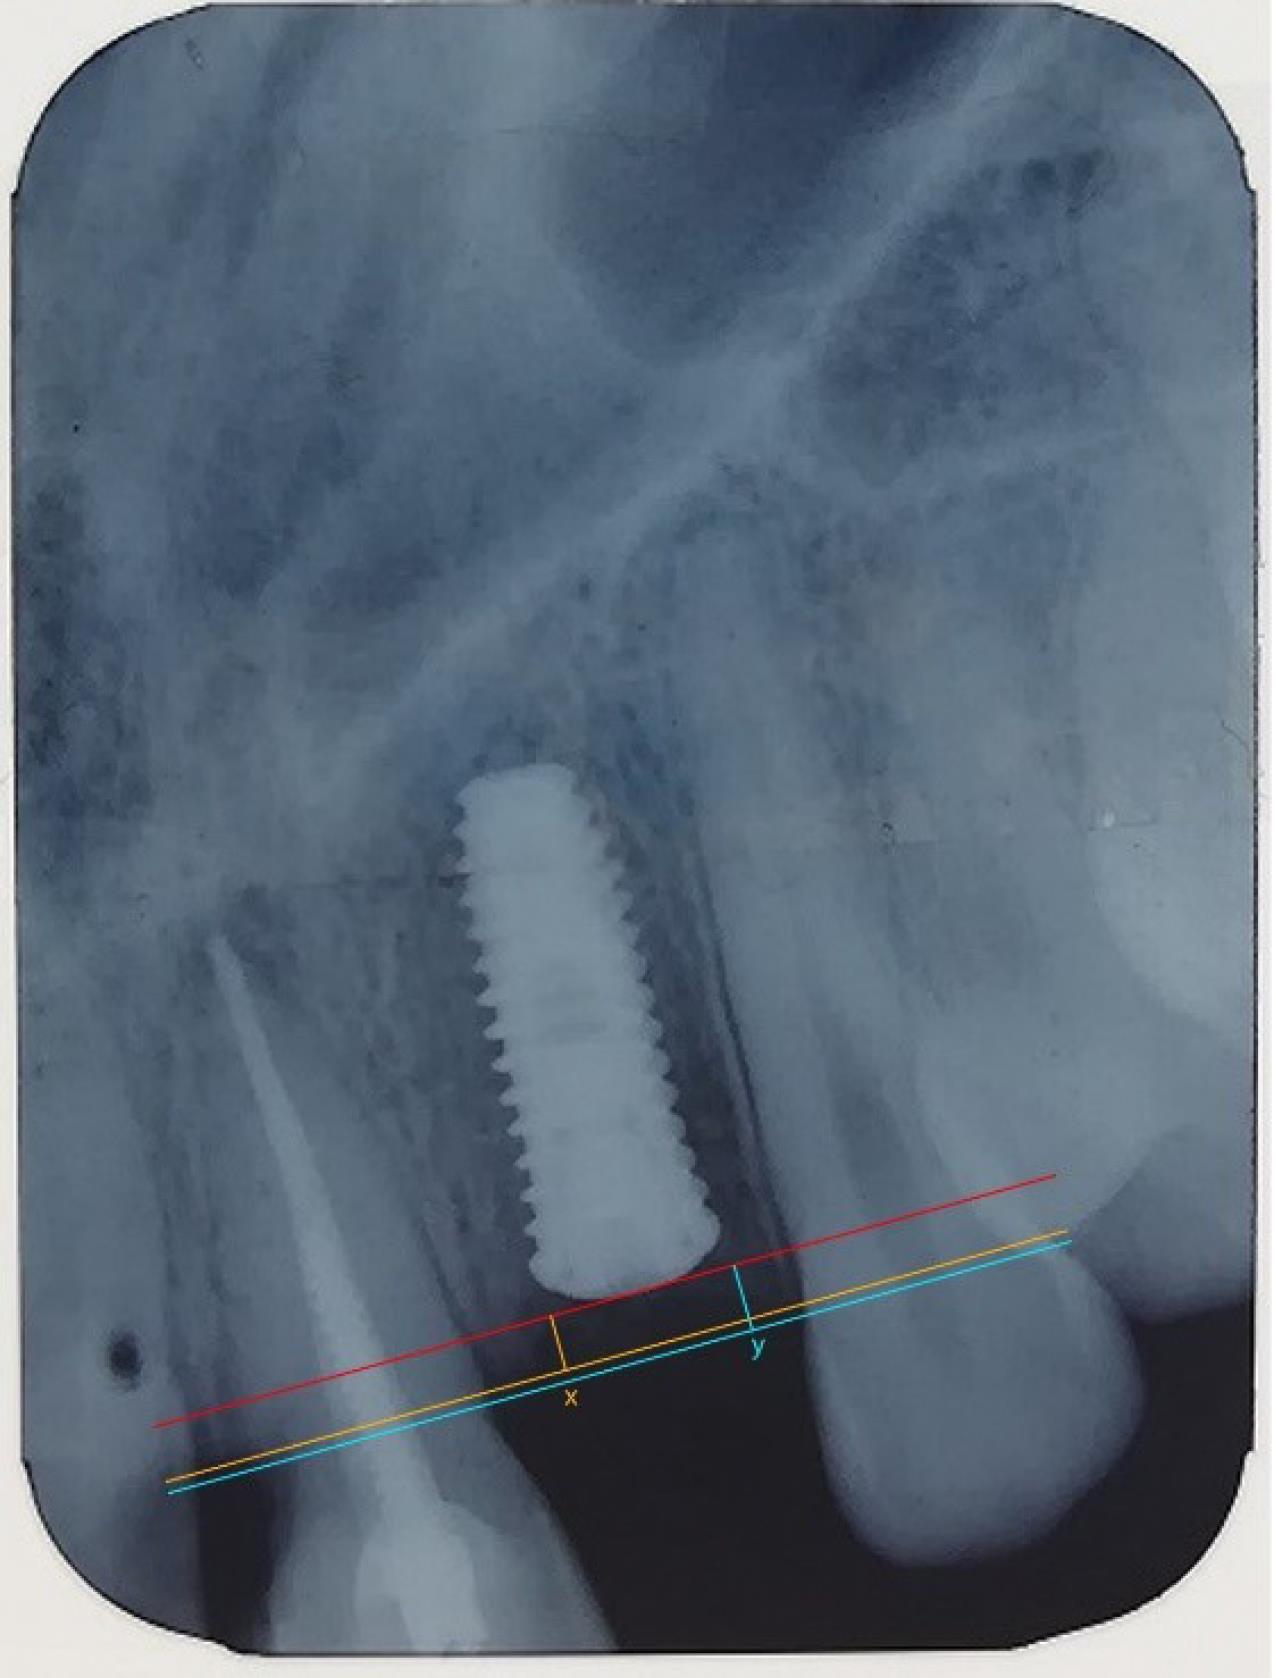

Since the length of the implant used was identified, it was possible to use this length to calibrate the image in computer software. The coronal implant surface was considered the reference line. Two lines were drawn parallel to this line from the crestal bone ridge between the implant and adjacent teeth on both the mesial and distal sides of the implant, and the distance between the two lines and the reference line was measured (Figure 6). By decreasing the bone measurement immediately after implantation and six months later, the amount of bone resorption was achieved on both the mesial and distal sides of the implant (Figure 7).5,13

Figure 6.

Measurement of crestal bone level from the reference line

Figure 7.

Comparison of crestal bone resorption (at 0 month and 6 months)